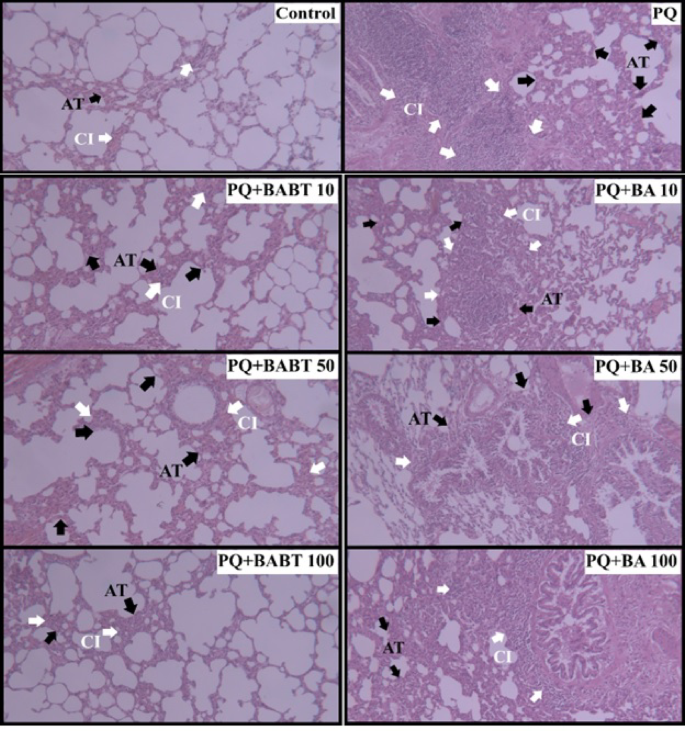

Evaluation of the H&E-stained and Masson’s Trichrome-stained sections revealed that the normal lung architecture was destroyed following PQ administration, and a fibrotic pattern was observed. The tissue photomicrographs in the control group displayed ideal lung architecture. In the PQ group, extensive tissue damage was evident, with destroyed alveoli, thickening of the alveolar wall, accumulation of inflammatory cells, atelectasis, and lung fibrosis. The tissue images of the PQ group treated with BABTs showed significant recovery with a considerable decrease in the fibrosis score. No observable differences in pathological changes were noted between the BABT-treated groups. No significant restoration was observed in the PQ group treated with BA, with the tissue structure remaining similar to that of the PQ group, showing alveolar destruction, atelectasis, accumulation of inflammatory cells, and thickening of the alveolar walls (Table 1).

The Szapiel score of the PQ group exhibited a statistically significant increase compared to that of the normal control group (P < 0.0001). In contrast, the Szapiel scores of the BABT10 and BABT50 treated groups showed a significant decrease (P < 0.05), while the BABT100 treated group displayed an even more pronounced reduction (P < 0.001) compared to the PQ group. These findings indicated the anti-inflammatory properties of BABTs. Conversely, the BA-treated groups did not demonstrate a notable decrease in Szapiel scores, suggesting that BA did not yield a significant anti-inflammatory effect on PQ-intoxicated rats (refer to Fig. 9 and Table 2).

H&E-stained histological evaluation of rat lungs in the Control, Paraquat (PQ), Paraquat with Boric acid-functionalized Bentonite nanostructures (PQ + BABT), and Paraquat with Boric acid (PQ + BA) groups on day 14 after PQ administration (× 100 magnification, Scale bar= 200 µm). Compared with the Control group, PQ intoxication showed progressive atelectasis and accumulation of inflammatory cells (chronic inflammation) in the alveolar space and septum. BABT nanostructures-treated groups showed remarkably decreased atelectasis (AT) and chronic inflammation (CI), while these changes were no less in the BA-treated groups.